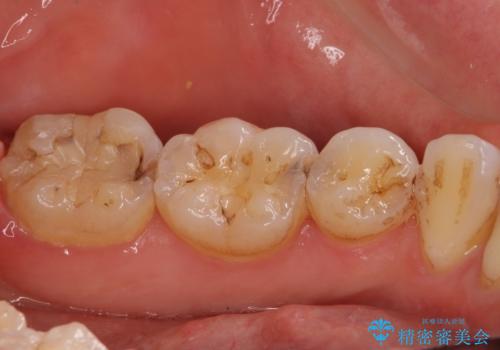

- 下の奥歯に虫歯ができてしまったとのことで来院された患者様です。

他にも気になる歯はありましたが、急を要する1歯のみをセラミックインレーにて修復治療を行うこととしました。

奥歯において、隣の歯と接触する部分に虫歯が及んでしまった場合、その場で充填を行う処置(コンポジットレジン修復)ですと、充填の縁に大きなギャップが生じてしまう可能性が高く、2次的な虫歯を引き起こすことになります。

また、処置した歯の後方にある歯は保険診療で使用するレジンインレーが装着されていますが、縁に虫歯が出来はじめていることが分かります。